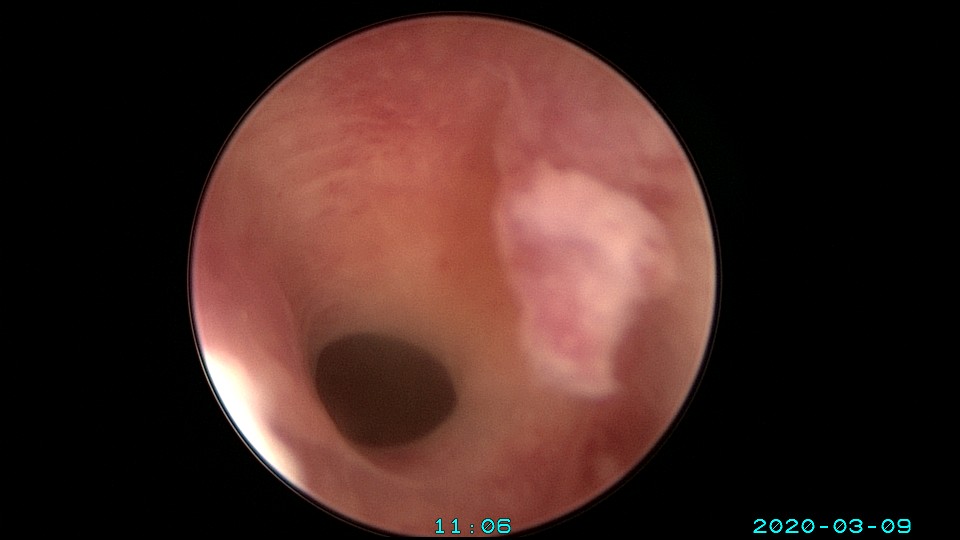

患者36岁,G3P0,自然流产3次,发现宫腔粘连3个月。2020年3月宫腔镜探查,子宫前倾后屈位,宫深8.5cm,宫颈管粘连狭窄,扩宫进入宫腔,见宫腔中下段两侧壁粘连,剪刀及双极电切分粘,宫腔形态恢复正常,双侧输卵管开口显露。2020年4月宫腔镜二探取球囊,宫腔形态正常,双侧输卵管开口可见。2021年6月自然妊娠,2022年2月足月剖宫产分娩。现42岁,G4P1。